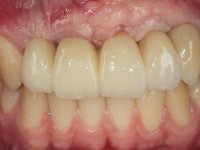

O paciente foi observado conjuntamente e a dúvida que surgiu de imediato foi se seria possível com a regeneração óssea a efectuar poder ser reabilitada naturalmente a zona das papilas interdentárias. Nesse sentido foi feito um enceramento de diagnóstico que contemplaria as duas hipóteses, utilizando ou não a cerâmica gengival. A confecção desse enceramento foi fundamental para expor ao paciente a dificuldade da reabilitação. O wax-up deu origem a um mock-up que foi aprovado pelo paciente e que simultaneamente serviu de guia imagiológica. O caso foi planificado cirurgicamente e realizada uma guia cirúrgica com que foram colocados os implantes. Após 10 semanas foi feita a 1ª impressão para confecção da ponte provisória. Foram criados os primeiros perfis de emergência na gengiva artificial e foi digitalizado o modelo. Por processo de CAD-CAM foi confeccionada uma ponte provisória aparafusada baseada no enceramento de diagnóstico. A ponte trabalhou durante 8 semanas os tecidos moles que foram fielmente copiados numa impressão com técnica de moldeira aberta. Os transferes foram individualizados com resina composta para copiarem fielmente os perfis de emergência criados pela ponte provisória. Confeccionado o modelo de trabalho definitivo, foi realizada uma infra-estrutura em zircónio seguindo a orientação do enceramento de diagnóstico. O assentamento da infra-estrutura foi testado em boca e simultaneamente foi novamente impressionados os tecidos moles com um silicone fluido. Nessa consulta foi feito o levantamento da cor. Os dentes 13 e 23 apresentavam uma saturação anormalmente forte que resolvemos não valorizar, optando por privilegiar a relação com o sector antero-inferior. Foi realizada uma nova gengiva artificial com a impressão que acompanhou a impressão de arrasto com a infra-estrutura. Após a colocação da cerâmica na infra-estrutura foram coladas as meso-estruturas. O trabalho final foi aparafusado lentamente permitindo a adaptação dos tecidos moles.